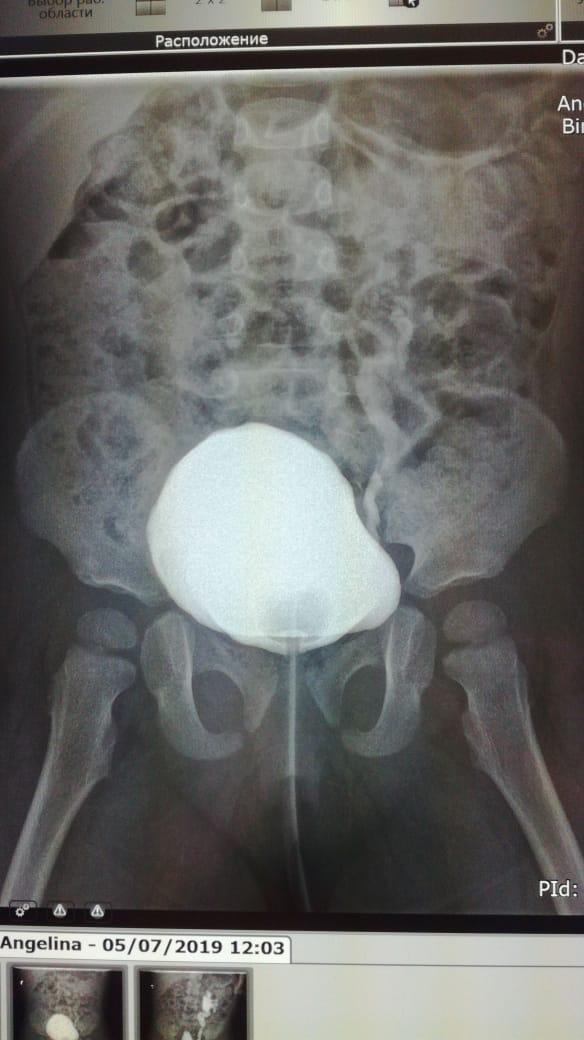

ПМР 4 степени

Здравствуйте.Моему ребенку 14.09.17г.р.была сделана вторая эндоскопическая коррекция ПМР 4 ст. в академии педиатрии СПб 07.06.19,(хотя рекомендовали и квоту одобрили на сложную операцию).08.06.19нас выписали.11.06.19г. ОАМ -удельный вес 1.006; лейкоциты 500(654,9); бактерии 13117,9;мочиться стала ещё реже 3 раза в день.17.06.19 были на приеме у нефролога,кот.нас направил обратно к урологам Академии педиатрии.Зав.отд.,посмотрев ОАМ и выписку ,спросил что я от него хочу...что ОАМ ещё ни о чем не говорит.Назначил прием Фурагина 3 раза в день по 50 мг в теч.месяца.А Вы как считаете,что лучше при такой степени рефлюкса,если почки уже страдают.